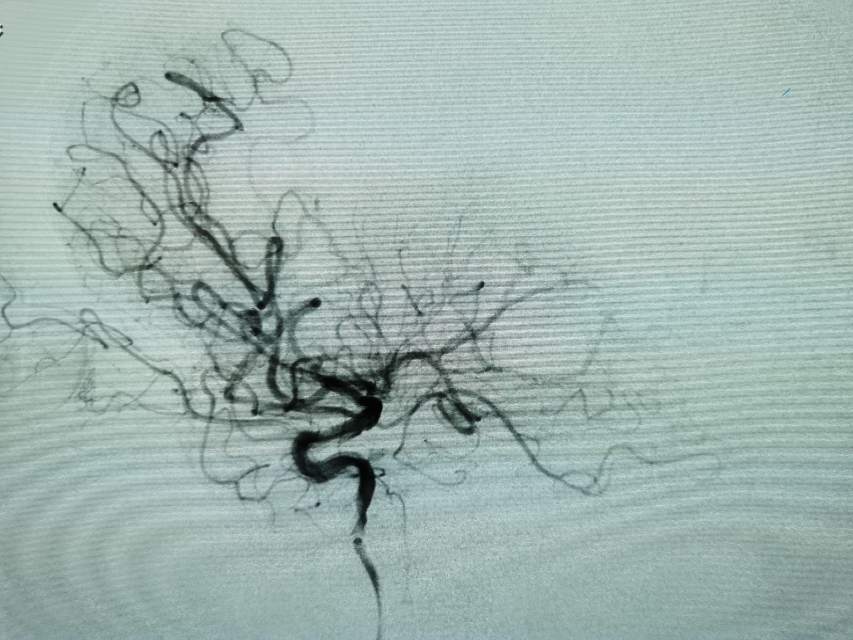

河南信阳帅哥,一个半月前突然出现左侧肢体肌力乏力、认知功能大幅下降、反应迟钝,在当地多家医院按照“脑梗塞”诊治后,症状未能缓解,仍呈进行性加重。经推荐转至我院寻求治疗,术前谈话之后,疫情期间,家里有急事需要处理,唯一的陪人回家了……。今日为患者手术,术中发现右侧大脑中动脉的一个分支出现多节段、长节段的夹层,血流仅剩断断续续的一条线,在血中飘摇,随时存在血管完全闭塞,脑梗塞继续加重,重者可能危及患者生命……,术中正确辨别真腔(误判后果严重),顺利打通重建血管,血流恢复……,手术只是整个治疗过程的一小部分,围手术期仍需要再接再励,帮助患者渡过风险期~~~